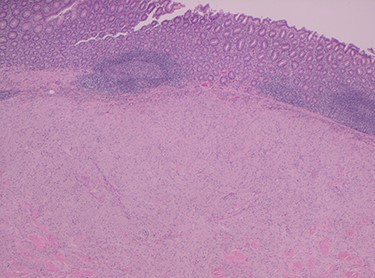

Histopathology of the right hemicolon found five firm nodules in the caecum and an additional seven polyps in the ascending colon macroscopically. Microscopically, a total of eight lesions in the caecum and ascending colon were found to be GCTs, varying in size from 1 to 7 mm. They were submucosal with intact covering mucosa (Figs 1 and 2). Tumour cells had periodic acid-Schiff (PAS)-positive granular cytoplasm and small nucleoli (Fig. 3). Immunohistochemical staining was positive for S-100 (Fig. 4) and inhibin. Twenty-four lymph nodes identified showed no abnormality. Spindling was seen in some tumours in this case, but overall, there are less than three worrisome features, and as such, these GCTs were considered atypical. Other polypoid lesions identified included two hyperplastic polyps and a submucosal lipoma.